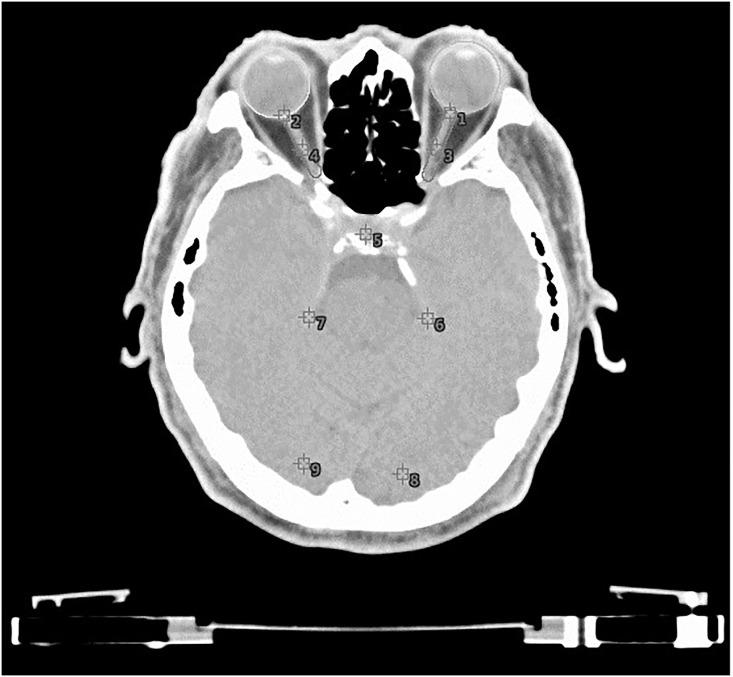

This study aimed to investigate the possible incidence of visual light perceptions (VLPs) during radiation therapy (RT). We analyzed whether VLPs could be affected by differences in the radiation energy, prescription doses, age, sex, or RT locations, and whether all VLPs were caused by radiation. From November 2016 to August 2018, a total of 101 patients who underwent head-and-neck or brain RT were screened. After receiving RT, questionnaires were completed, and the subjects were interviewed. Random forests (RF), a tree-based machine learning algorithm, and logistic regression (LR) analyses were compared by the area under the curve (AUC), and the algorithm that achieved the highest AUC was selected. The dataset sample was based on treatment with non-human units, and a total of 293 treatment fields from 78 patients were analyzed. VLPs were detected only in 122 of the 293 exposure portals (40.16%). The dataset was randomly divided into 80% and 20% as the training set and test set, respectively. In the test set, RF achieved an AUC of 0.888, whereas LR achieved an AUC of 0.773. In this study, the retina fraction dose was the most important continuous variable and had a positive effect on VLP. Age was the most important categorical variable. In conclusion, the visual light perception phenomenon by the human body during RT is induced by radiation rather than being a self-suggested hallucination or induced by phosphenes.

本研究旨在探讨放射治疗(RT)期间视觉光感知(VLP)的可能发生率。我们分析了 VLP 是否会受到辐射能量、处方剂量、年龄、性别或 RT 部位的差异影响,以及所有 VLP 是否都是由辐射引起的。

2016 年 11 月至 2018 年 8 月,筛选了 101 例接受头颈部或脑部 RT 的患者。接受 RT 后,完成问卷调查并对受试者进行访谈。采用曲线下面积(AUC)比较随机森林(RF)和逻辑回归(LR)分析,选择 AUC 最高的算法。

数据集样本基于非人体单位的治疗,共分析了 78 例患者的 293 个治疗野。仅在 293 个照射端口中的 122 个(40.16%)检测到 VLP。数据集随机分为 80%和 20%作为训练集和测试集。在测试集中,RF 的 AUC 为 0.888,而 LR 的 AUC 为 0.773。

在本研究中,视网膜分剂量是最重要的连续变量,对 VLP 有正向影响。年龄是最重要的分类变量。

总之,人体在 RT 过程中产生的视觉光感知现象是由辐射引起的,而不是自我暗示的幻觉或由光幻视引起的。